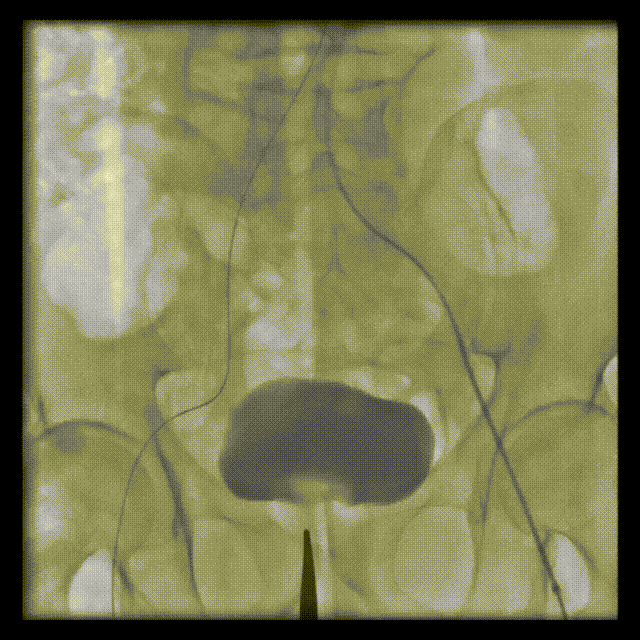

术前CT

患者是73岁男性,因“反复咳嗽、咳痰伴气喘超过5年,近期症状加重”入院,入院诊断为主动脉瓣重度狭窄伴轻-中度反流、慢性心力衰竭(心功能Ⅲ级)、慢性阻塞性肺疾病等。综合超声、CT评估结果,该患者年龄较高、合并症多、体质差,无法耐受外科开胸手术,经过多学科会诊综合评估临床获益与风险,决定为其行TAVR手术(经导管主动脉瓣置换术)。